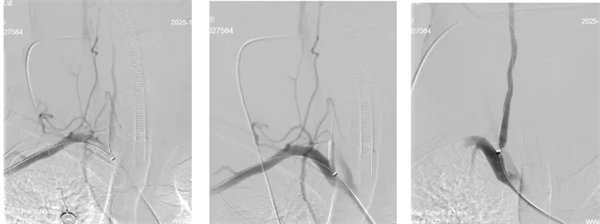

術中,介入團隊精準定位血管閉塞部位,通過微導絲“探路”聯合球囊擴張技術開通右側椎動脈開口,造影椎開口殘余狹窄60%?;讋用}血栓形成,基底動脈管腔狹窄55%,基底動脈尖堵塞,右側大腦后動脈及小腦上動脈未見顯影,左側大腦后動脈P3以遠閉塞。

席聰準確鎖定患者基底動脈處血栓,采用抽吸取栓技術快速開通血管,成功取出堵塞部位2cm的血栓。再次造影示:右側大腦后及雙側小腦上動脈再通,右側大腦后動脈P3段以遠閉塞,考慮慢性閉塞,推注替羅非班,血流明顯加快。隨后采用支架植入術開通右側椎動脈開口處,術中影像顯示:支架貼壁良好,無明顯殘余狹窄,顱內血管顯影良好。